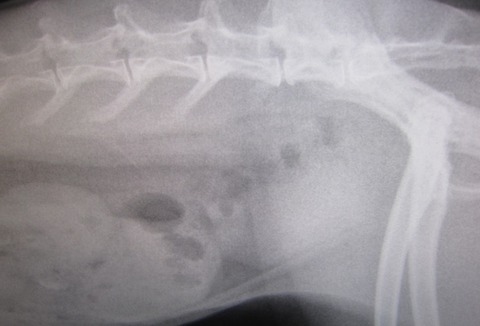

昨夜からの流れを話しし、診察、レントゲン

閉塞所見はありません

もちろん心臓も小さくなってないし

若干のガスはあれど、強いて指摘するならばレベル

で、ちゃんと出番待ちしとる(。・m・)

いつも感心するウンコ影“〆( ̄▽ ̄*)

と、胃腸に大きな問題はなさげだったのだが…

脂肪、すご過ぎやん…( ̄ェ ̄;)

前回との比較…

前回… とは、最初、あんまりにも食べない食べないで、きちんと痩せた状態、だったので余計かもですが、それでもマズい…